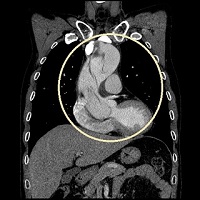

건국대학교병원 대동맥·혈관센터(센터장 김준석 흉부외과 교수)는 24시간 전문의가 상주하며, 현대사회에서 가장 빠르게 증가하고 있는 대표적인 질환인 대동맥 질환(대동맥 박리증, 대동맥류 및 대동맥 근부 질환 포함) 및 혈관질환(말초 동맥, 말초 하지정맥류) 환자를 원스톱시스템으로 신속하게 치료하는 건국대병원의 대표적인 특수센터다.

대동맥, 혈관 질환은 과거에는 수술로만 치료가 가능했으나 현재는 3D CT 등의 도입과 하이브리드 수술실 등이 발전하여 영상의학과 또는 내과에서 인터벤션 기법을 통한 스텐트 그라프트 시술 등으로 치료하는 빈도가 증가하고 있으며, 건국대병원 대동맥·혈관센터도 최근 3년간 인터벤션 기법으로 대동맥 및 혈관을 치료한 례가 2배 이상 증가했다.